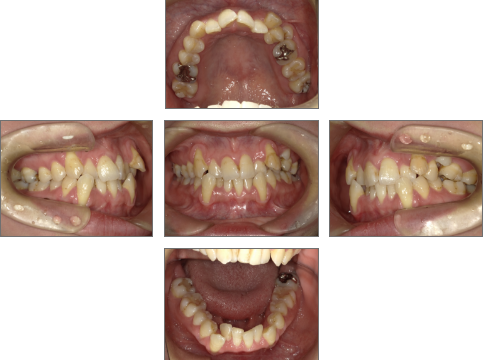

【治療前】

●主訴

歯並びのガタガタが気になる。歯磨きがしづらく、将来、歯が悪くなってしまうのではないか、心配。

●診断名あるいは主な症状

叢生

●年齢

31歳2ヶ月

●治療に用いた主な装置

セラミックブラケット

●抜歯部位

右上4番、左上6番、右下4番、左下4番・8番(親知らず) 計5本抜歯

●治療期間

約2年

●メンテナンス頻度

月1回

●治療費用(税抜)

約1,100,000円